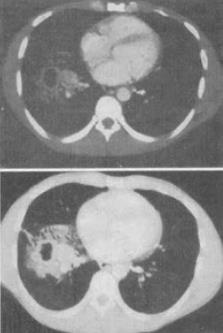

5、 患者男,64岁,患糖尿病,最近3天出现发热,伴颈静脉显露,结合CT图像,最可能的诊断是()。

- A、坏死性纵隔炎

- B、纵隔淋巴瘤

- C、侵袭性胸腺瘤

- D、恶性畸胎瘤

- E、纵隔脓肿

【正确答案-参考解析】:参加考试可见 点击进入查看